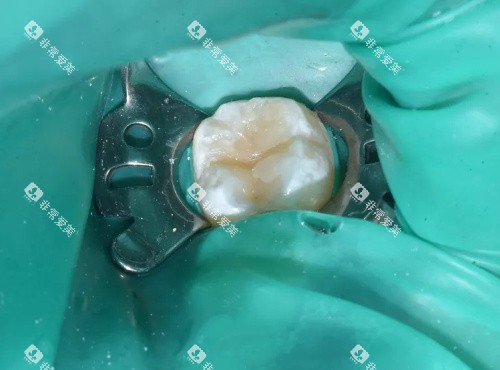

根管治疗是治疗牙髓炎、根尖周炎等牙髓疾病的有效方法。

佛山莞口口腔连锁医院根管治疗收费410元起。

根管治疗的费用也与多种因素有关。

牙齿部位

不同部位的牙齿,其根管数量和复杂程度不同,治疗费用也会有所差异。

一般来说,前牙的根管数量较少,治疗相对简单,费用较低;而磨牙的根管数量较多,且根管形态复杂,治疗难度较大,费用相对较高。

治疗难度

有些患者的根管可能存在钙化、弯曲等情况,增加了治疗的难度,需要医生花费更多的时间和精力进行治疗,费用也会相应提高。

此外,如果根管治疗过程中出现并发症,如根管侧穿等,需要进行额外的处理,费用也会有所增加。